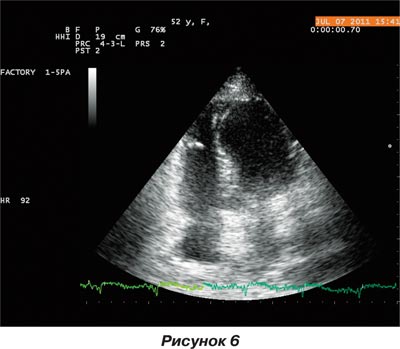

Оперативное вмешательство по устранению дефекта межжелудочковой перегородки проведено успешно. Больная в удовлетворительном состоянии переведена в ННЦ «Институт кардиологии им. Н.Д. Стражеско» в отделение инфаркта миокарда и восстановительного лечения. При проведеннии эхокардиографического исследования выявлено закрытие места разрыва межжелудочковой перегородки тканью обтуратора, кровоток между левым и правым желудочками сердца минимальный (рис. 6, 7).